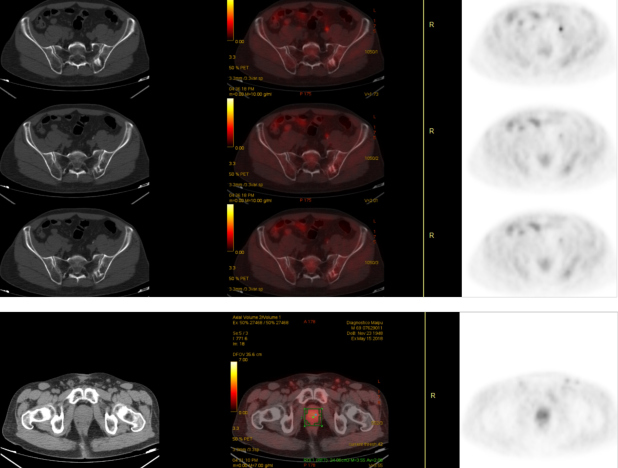

Hombre de 69 años, atleta, con diagnóstico reciente de adenocarcinoma de próstata, Gleason 3+3, PSA 4,2 ng/ml, al que se realiza centellografía ósea para estadificación (fig.1). Se observó la presencia de imagen hipercaptante única en tercio medio de la unión sacroilíaca izquierda. Este foco se correspondió con imagen lítico-blástica por CT en la porción posterior del ilíaco izquierdo, adyacente a la articulación sacroilíaca. Posteriormente se realiza estudio PET/CT F18-colina para descartar o confirmar carácter maligno de la lesión en base a su afinidad por el radiofármaco. Se comprobó captación leve de F18-colina en la lesión, consistente con proceso inflamatorio no tumoral (fig. 2). Se interpretó como geoda acompañada de reacción inflamatoria local. El tumor primario de próstata, a su vez, presentó captación intensa del trazador.